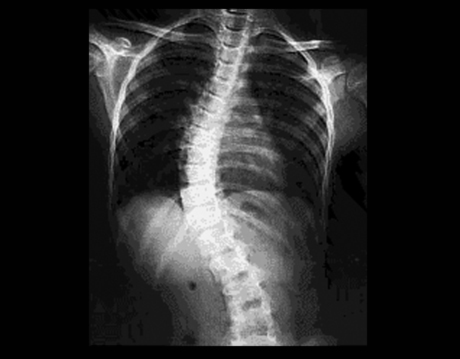

Your choice: Scoliosis

This chest X ray shows scoliosis. In this PA view, the primary curve is in the mid and lower thoracic region and, as shown here, is more commonly convex to the patient's right than to the left. The right heart border is superimposed upon the vertebral column so that its outline is obscured. This makes the heart appear enlarged.